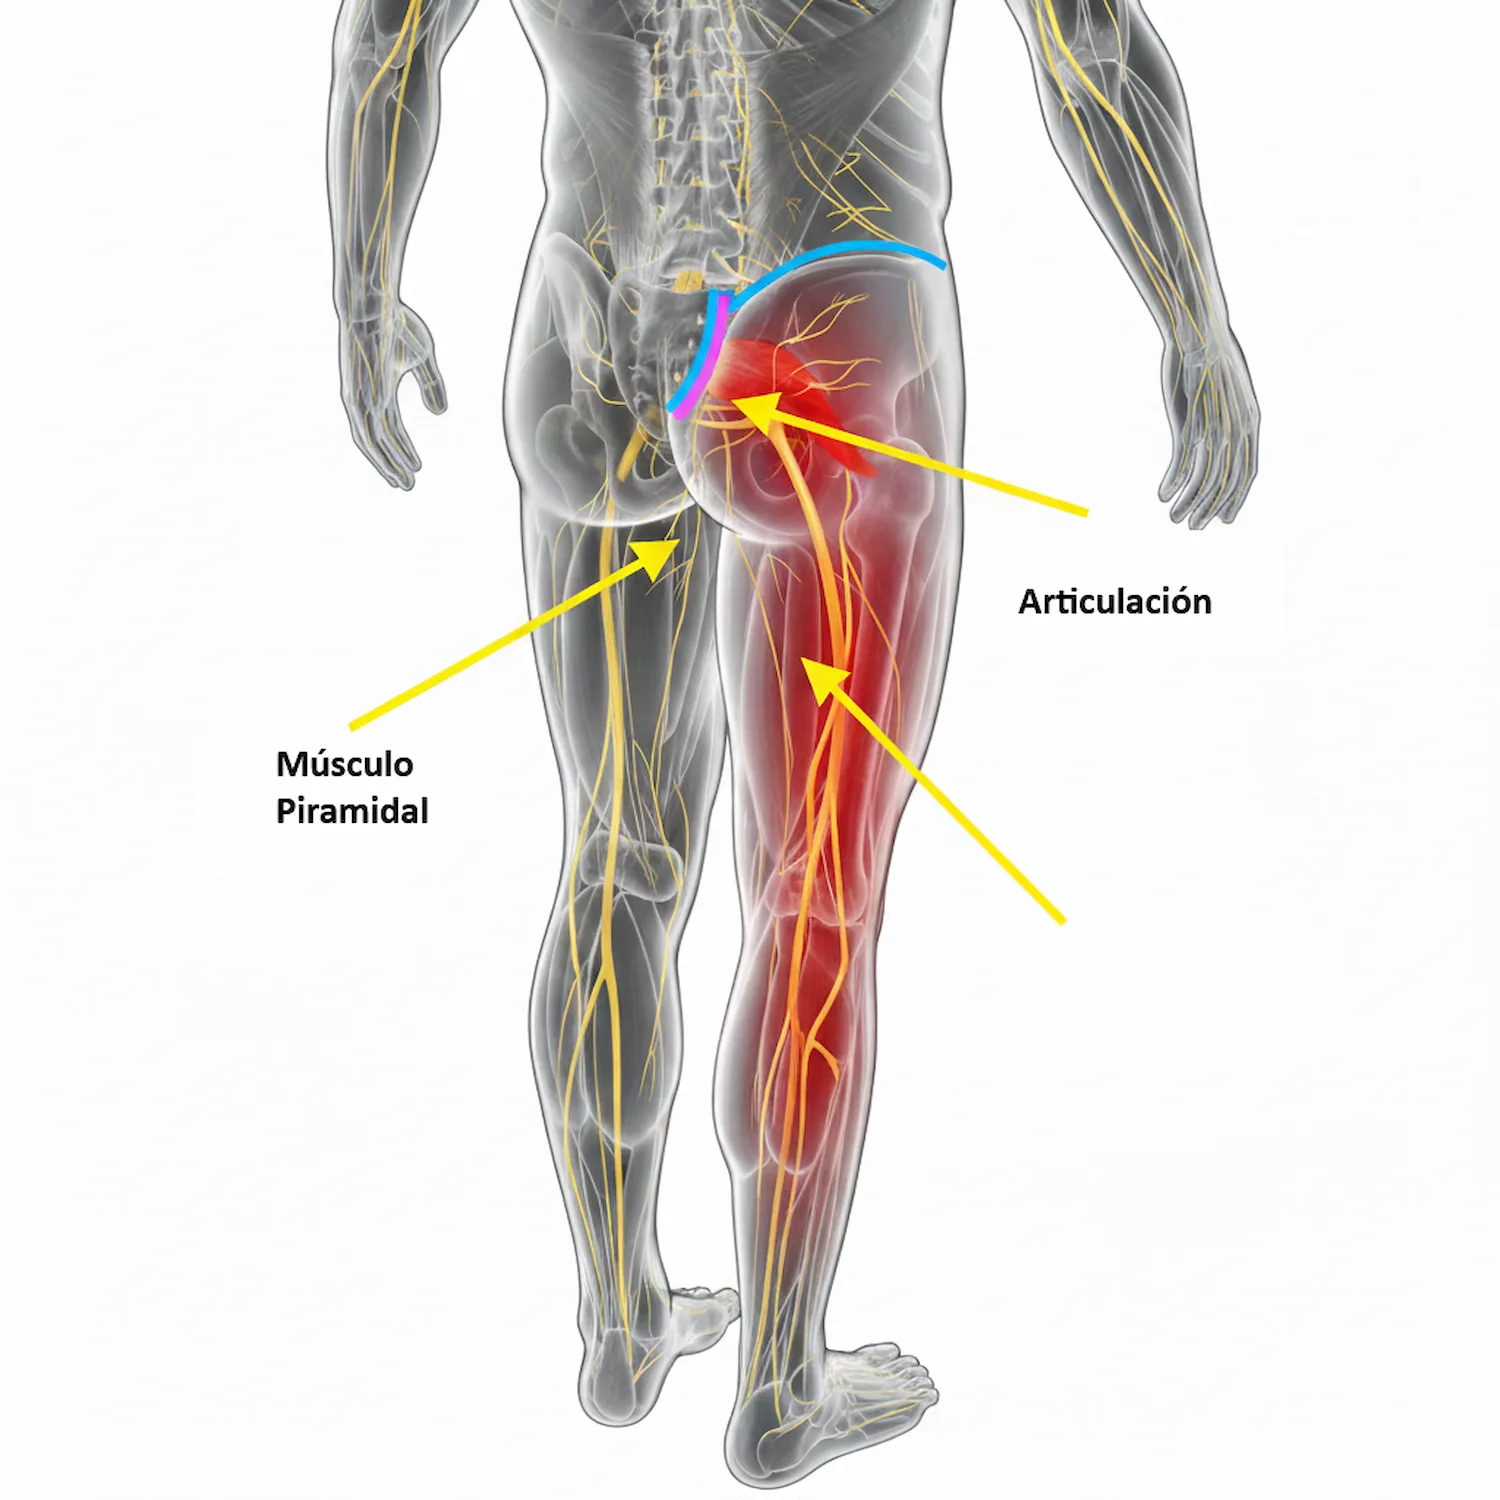

Síndrome Piramidal: Qué es, causas, tratamiento efectivo y recomendaciones para deportistas

El dolor en el glúteo puede ser más que una simple molestia. Aprende qué es el síndrome piramidal, cómo identificarlo y tratarlo eficazmente con estrategias modernas de fisioterapia y prevención deportiva.